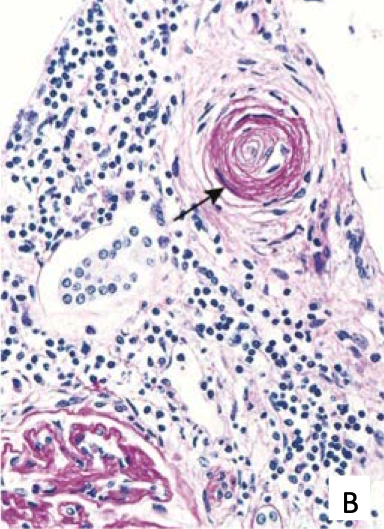

Hyperplastic arterioloscerosis due to malignant hypertension